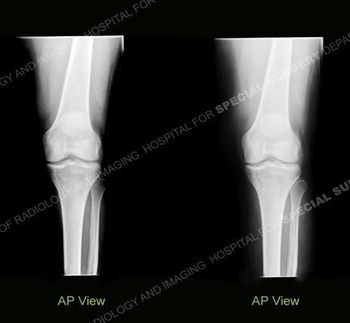

Images taken 7 months apart show subtle densities of the left knee that has been causing pain. The woman also has subluxation of the fingers, without erosion.